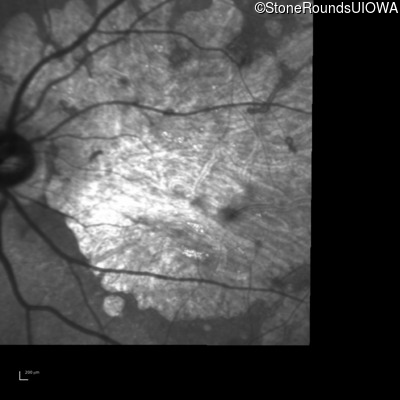

Infrared Fundus Photograph - Left - 5/400

Exemplar